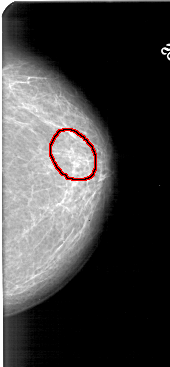

FILE: A_1433_1.RIGHT_CC.OVERLAY

TOTAL_ABNORMALITIES 1

ABNORMALITY 1

LESION_TYPE CALCIFICATION TYPE PUNCTATE DISTRIBUTION SEGMENTAL

ASSESSMENT 2

SUBTLETY 3

PATHOLOGY BENIGN

TOTAL_OUTLINES 1

BOUNDARY